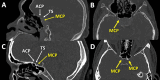

Background The middle clinoid process (MCP), particularly caroticoclinoid ring (CCR) type of the MCP, is an important part of the sphenoid bone for skull base surgery. Previous studies have shown a wide range of MCP prevalence affected by various factors. However, no study has investigated the association between the MCP and the presence of sellar lesions. Objectives The main aim of this study was to evaluate the prevalence of the MCP in the Thai population and factors associated with its presence. Materials and Methods We conducted a cross-sectional study on 400 sides from 200 patients (100 with and 100 without sellar lesions) using cranial computerized tomography scans. Demographic data and MCP characteristics were collected. The association between individual variables and the presence of the MCP was determined by univariate and multivariate analysis. Results The MCP was identified in 168 of 400 sides (42%). Patients with sellar lesions had a significantly lower prevalence of the MCP compared with normal controls (29.5% versus 54.5%, p < 0.001). Of all MCP only 6% were the CCR type. Univariate and multivariate analysis showed that the absence of the sellar lesion was the only factor significantly associated with presence of the MCP (odds ratio: 2.86; 95% confidence interval: 1.90-4.32; p < 0.001). Conclusion The prevalence of the MCP was relatively high in the Thai population, while the prevalence of the CCR was relatively low compared with previous studies. The absence of sellar lesions was the only factor associated with the presence of the MCP.